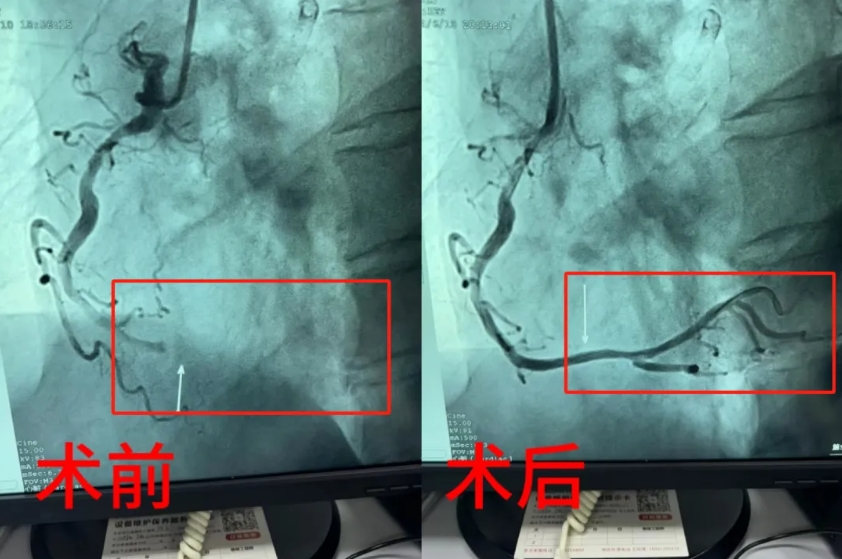

6月9日,一名61岁的男性患者因剑突下疼痛并放射至左上肢,伴有心悸、呼吸困难和大汗淋漓等症状。随后,患者还出现了短暂的晕厥,自行苏醒后患者自觉症状不缓解,对病情高度重视并就诊于我院胸痛中心。完善心电图检查,诊断为急性心肌梗死。面对患者复杂的病情和严重的血栓负荷,胸痛中心立即为患者实施介入治疗,冠脉造影示:前降支近段至中段弥漫性性病变最狭窄95%,回旋支近中段迂曲,狭窄90%,中远段完全闭塞,右冠脉近中段弥漫性长病变,最重处狭窄65%。在手术过程中,患者心率一度低至39次/分,血压也下降至98/80mmHg。医护人员迅速采取措施,患者心率和血压逐渐恢复正常。经过反复多次的冠脉内给药和精细操作,成功在患者左回旋支病变处置入了两枚支架。术后患者转入监护病房继续治疗,现生命体征平稳。

6月10日凌晨3时许,一名52岁的男性患者因睡眠时胸骨后疼痛、心悸和呼吸困难等症状,患者自认为是胃病发作,自行口服药物后症状未缓解,后就诊于我院胸痛中心。医护人员迅速接诊并完善心电图检查,诊断为急性非ST段抬高型心肌梗死。胸痛中心迅速为患者给予了药物治疗,然而患者症状仍未明显缓解。在与患者及家属充分沟通后,胸痛中心决定为患者实施急诊冠脉介入治疗,冠脉造影示:左主干中远段狭窄40%,前降支狭窄80%,回旋支狭窄50%,右冠脉远端完全闭塞。经过紧张的手术操作,成功在患者右冠病变处置入一枚支架,使患者症状得到缓解并转入病区继续后续治疗。